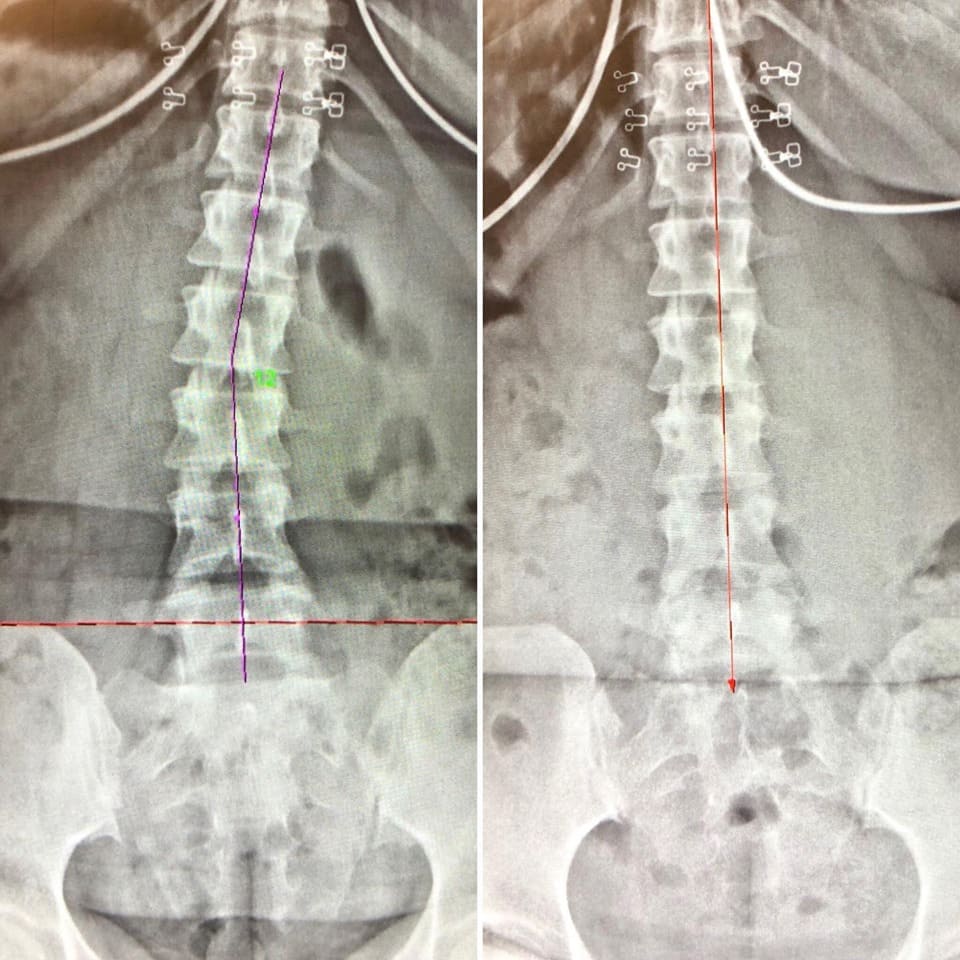

The Digital Posture X-Rays below are Before & After X-rays of practice members that got AMAZING RESULTS via our Corrective Care health program over the course of just 1 year!

By taking digital spine x-rays, chiropractors at Camarata Chiropractic can identify problems with the spine's alignment, detect bone density changes, and assess the degree of degeneration that may exist. This information helps chiropractors to identify underlying causes of spinal misalignment, such as injury or degeneration, and develop a treatment plan that addresses these issues. With the help of digital spine x-rays, chiropractors can also monitor the effectiveness of treatment over time, making any necessary adjustments to ensure that patients receive the best possible care.